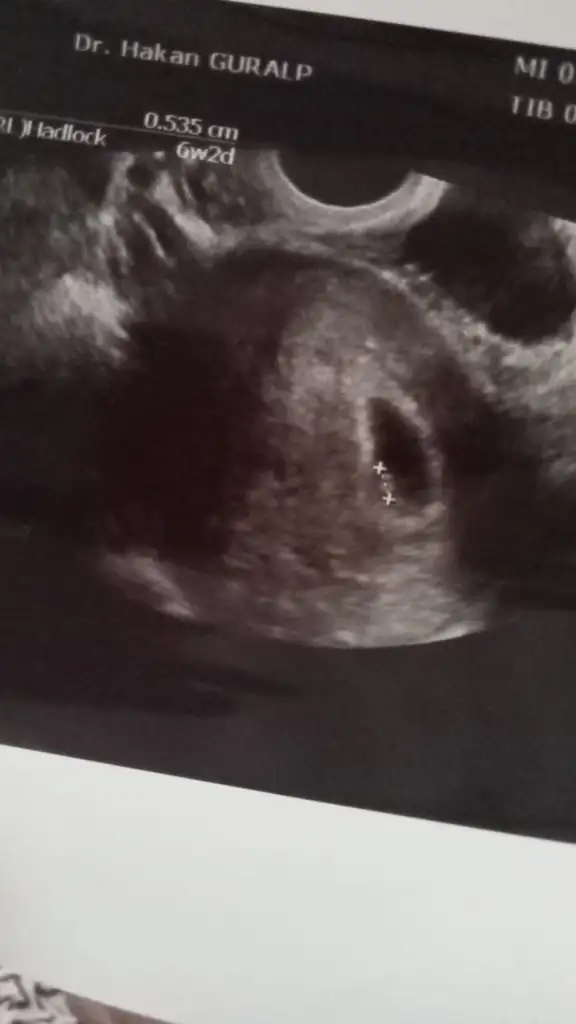

6+5 oldu bugün canım doktor 6+2 demişti o günMaşallah canim kaç haftaydı senin şuan benim bulantim filan hiçbişey yok şuan normal gibiyimbende ne zaman başlıycak diye merak ediyorum

Allah yardımcın olsun canım ya inşallah o. İyi olsun da ben herşeye razıyım :)6+5 oldu bugün canım doktor 6+2 demişti o günherkeste bulantı olmuyormuş ama benim midem baya hassas, senin de olursa iki üç haftaya başlar merak etme çubuk kraker stoklarsın